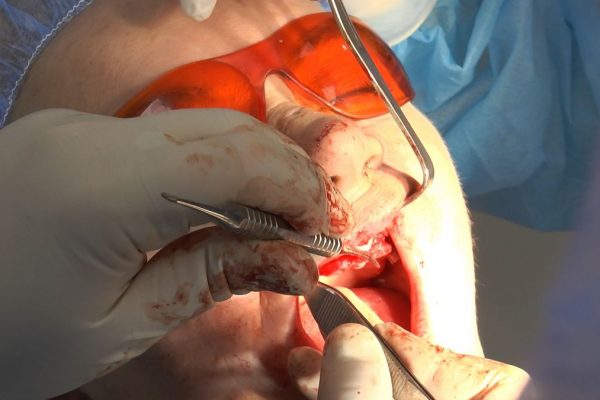

W ostatni weekend czerwca 2018 roku kursanci II Sezonu Preludium Implantologii odbyli piątą, finałową sesję, która w całości podporządkowana była praktyce. W ciągu dwóch dni zabiegowych Lekarze uczestniczący w szkoleniu przeprowadzili szereg zabiegów pod kierunkiem dr n.med. Violetty Szycik. Wszczepili 17 implantów oraz przeprowadzili ekstrakcje i zabiegi regeneracyjne kości. Zabiegi były wykonywane także w sedacji dożylnej z udziałem specjalisty anestezjologii i intensywnej terapii dr Jolanty Grzybowskiej. Preludium implantologii to nowy program edukacyjny dla adeptów implantologii stomatologicznej, którego celem jest wprowadzenie do implantologii poprzez pozyskanie wiedzy w szerokim zakresie i uwzględnieniem szczegółów mających decydujące znaczenie dla powodzenia leczenia implantologicznego. Ale tak jak wszystkie szkolenia w Instytucie Vivadental, w tym wiodące Practiculum Implantologii, zorientowane jest na praktyce i samodzielnym wykonywaniu zabiegów pod kierunkiem Mentora. To najlepsza edukacja w medycynie zabiegowej, a zarazem najlepszy start do implantologii.